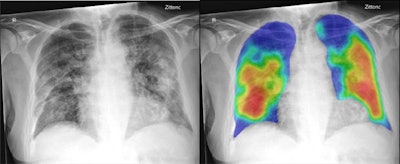

A free commercial artificial intelligence (AI) software application can perform comparably to radiologists in triaging suspected COVID-19 cases on chest radiographs, according to research published online May 8 in Radiology.

A team of researchers from the Netherlands and AI software developer Thirona reported that their software yielded an area under the curve (AUC) of 0.81 for detecting COVID-19 on a test of nearly 500 cases. It also performed similarly to six experienced radiologists.

Based on the previously released CAD4TB v6 deep-learning software for detecting tuberculosis on chest x-rays, CAD4COVID-Xray was developed and validated by Thirona using 24,678 chest x-ray images. It was then tested on 454 continuously acquired chest x-ray exams in patients suspected to have COVID-19 pneumonia at the Jeroen Bosch Hospital. Of these 454 patients, 223 had positive reverse transcription polymerase chain reaction (RT-PCR) assay findings for the SAR-CoV-2 virus, while 231 had negative results.

In addition to providing an AUC of 0.81, the software also outperformed each reader at their highest possible sensitivities (p < 0.001). Only one reader was able to significantly outperform the AI system (p = 0.04) at the lowest sensitivity setting of 65%.

At an 80% sensitivity setting, the CAD4COVID-Xray had a positive predictive value (PPV) of 68% and a negative predictive value (NPV) of 81%, compared with a 58% PPV and 72% NPV achieved by the reader consensus. At a 75% sensitivity setting, the AI software produced 77% PPV and 76% NPV, compared with 72% PPV and 76% NPV for the reader consensus.